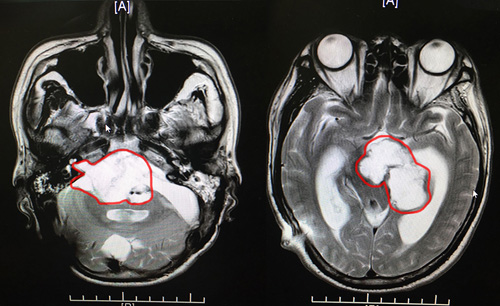

沈教授說:根據(jù)患者在藍(lán)十字做的核磁檢查報(bào)告,我們發(fā)現(xiàn)環(huán)池、橋前池,鞍上池,左側(cè)四疊體池占位,很有可能是腫瘤術(shù)后殘余。而且患者的左側(cè)后顱窩硬膜下和左側(cè)枕骨頭皮下都是積液,這個(gè)情況是必須要再做手術(shù)了。

患者術(shù)前影像:環(huán)池、橋前池,鞍上池,左側(cè)四疊體池占位